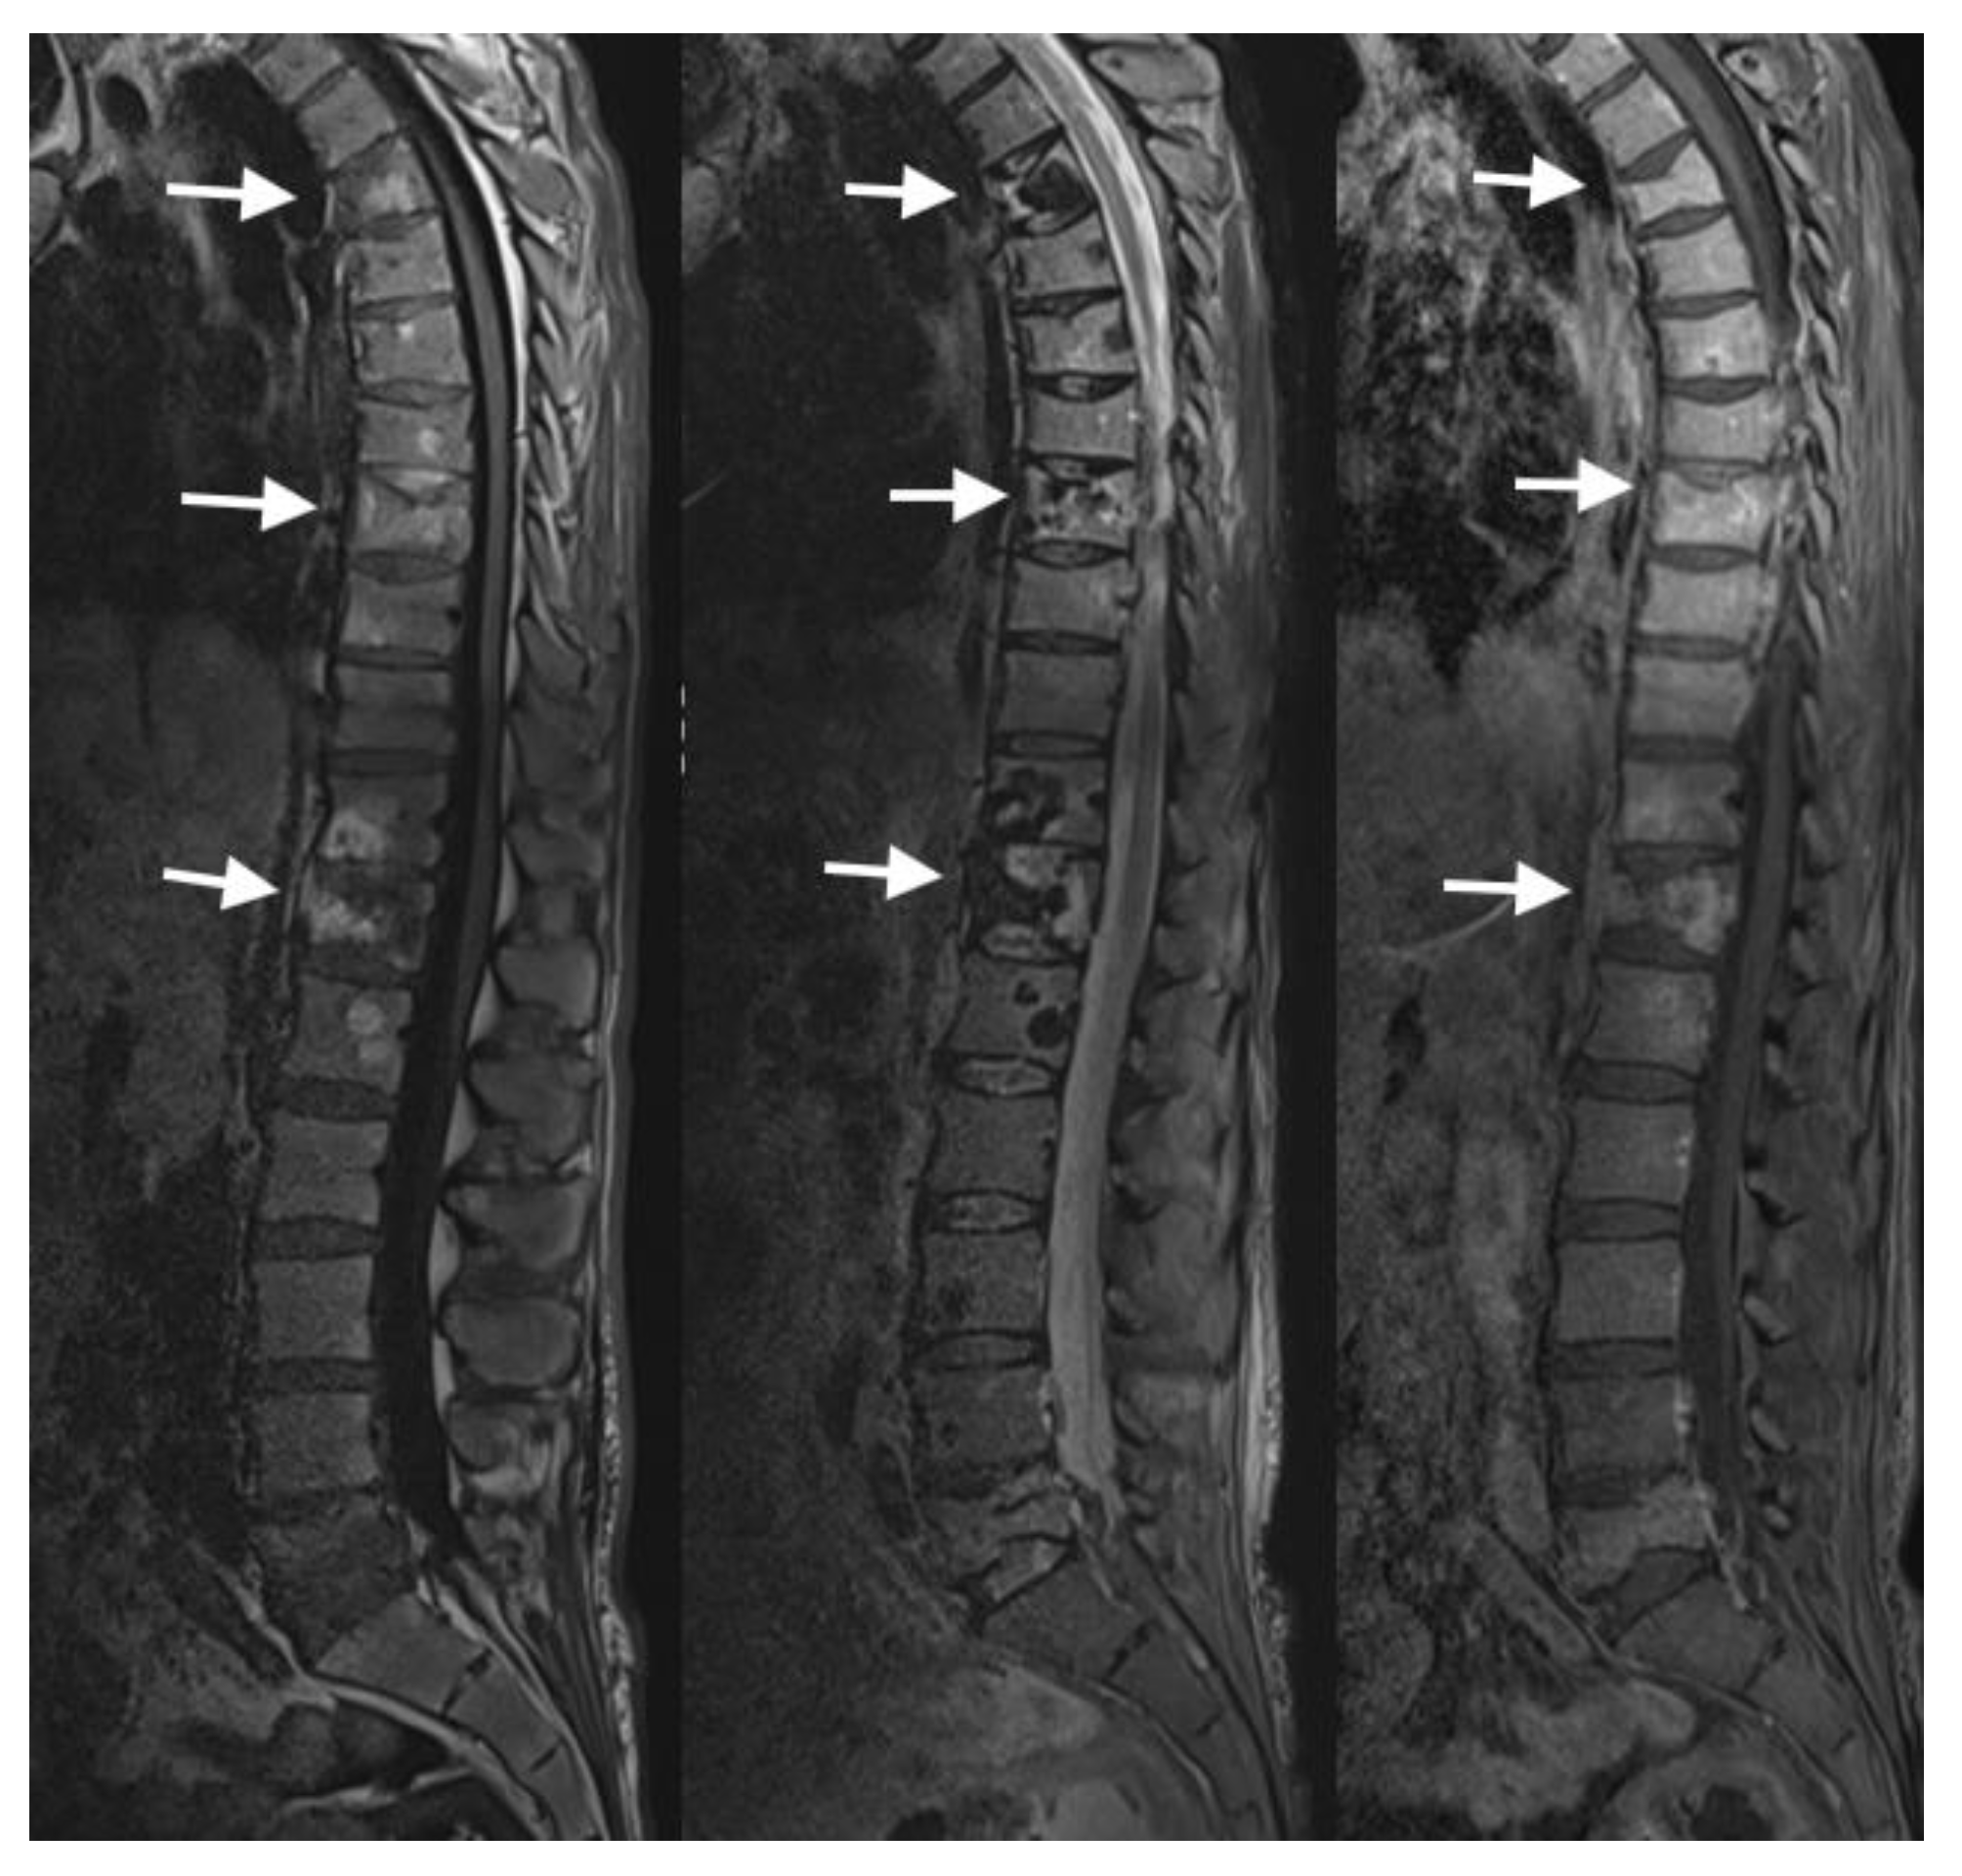

4.3. MRI Scans

4.4. Nuclear Medicine